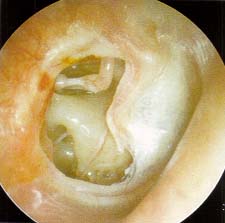

»ïÃ⼺ ÁßÀÌ¿° °í¸·»çÁø

Æ©ºê »ðÀÔ °í¸·»çÁø